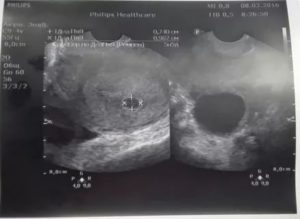

До 5 недель сформированное плодное яйцо очень мало – его размер составляет всего около двух миллиметров. Результативным методом диагностики эмбрионального периода считается именно трансвагинальный – его высокочастотный датчик дает возможность максимально приблизиться к маточной полости и передать на экран монитора мельчайшие размеры исследуемых органов.

Именно поэтому разница между реальным и акушерским сроком зачатия ребенка составляет две недели. У женщины репродуктивного возраста с нормальным менструальным циклом распознавание беременности при трансвагинальном исследовании происходит не позже пяти недель.

| Диагностирование эктопической беременности (вне полости матки) | 4–5 | 5–6 |

| Срок визуализации эмбриона | 5 | 6 |

| Шевеление плода | 5–6 | 7–8 |

| Мониторинг сердечной деятельности | 5–6 | 6–7 |

Начало сокращений сердечной мышцы будущего малыша приходится на срок с 3 до 4 недель и уловить его возможно только с помощью трансдюсера (специального узкого вагинального датчика). Случается, что врач-узист не может ничего разглядеть в плодном яйце и рекомендует прийти на обследование через 7–14 дней.

Именно частота сокращений мышцы сердца эмбриона позволит врачу уточнить срок гестации:

- в 5 акушерских недель частота сердечных сокращений составляет до 85 уд/мин;

- в 6 – от 102 до 126;

- в 7 – от 127 до 149;

- в 8 – от 150 до 172;

- в 9 – 175.